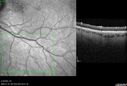

Hydroxychloroquine Toxicity70 x angesehen60 year old female received 6.5 mg/kg Plaquenil for 15 years and developed toxicity. VA 20/40 OD, 20/20 OS